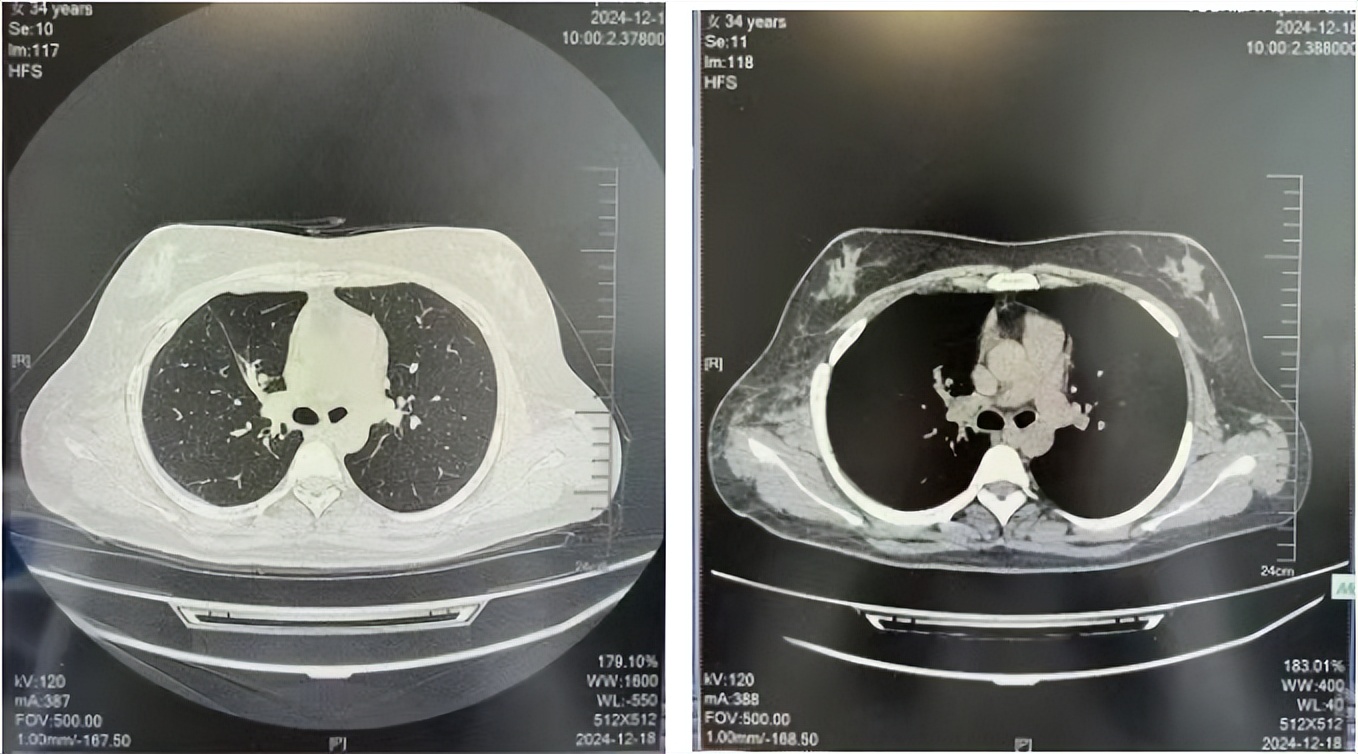

治疗经过:2023年3月27日始行恩沙替尼靶向治疗至今,最佳疗效为PR,末次评效为维持PR。期间出现轻度肝功能异常(DILI 1级),对症处理后好转。截止目前PFS为26个月。

2023年2月20日基线检查

2024年6月复查PR(最佳疗效)

2024年12月复查维持PR

2025年3月复查维持PR